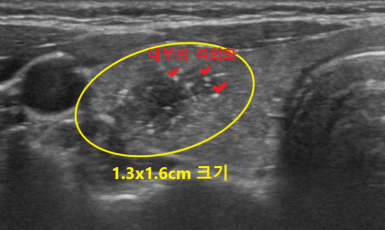

307번째 갑상선암 진단사례 (2019년8월14일) 왼쪽 유방통증이 있어 유방검사를 받기위해 내원해 주신 환자분이셨습니다. 검사를 위해 유방초음파를 받으셨는데 유방에서는 큰..